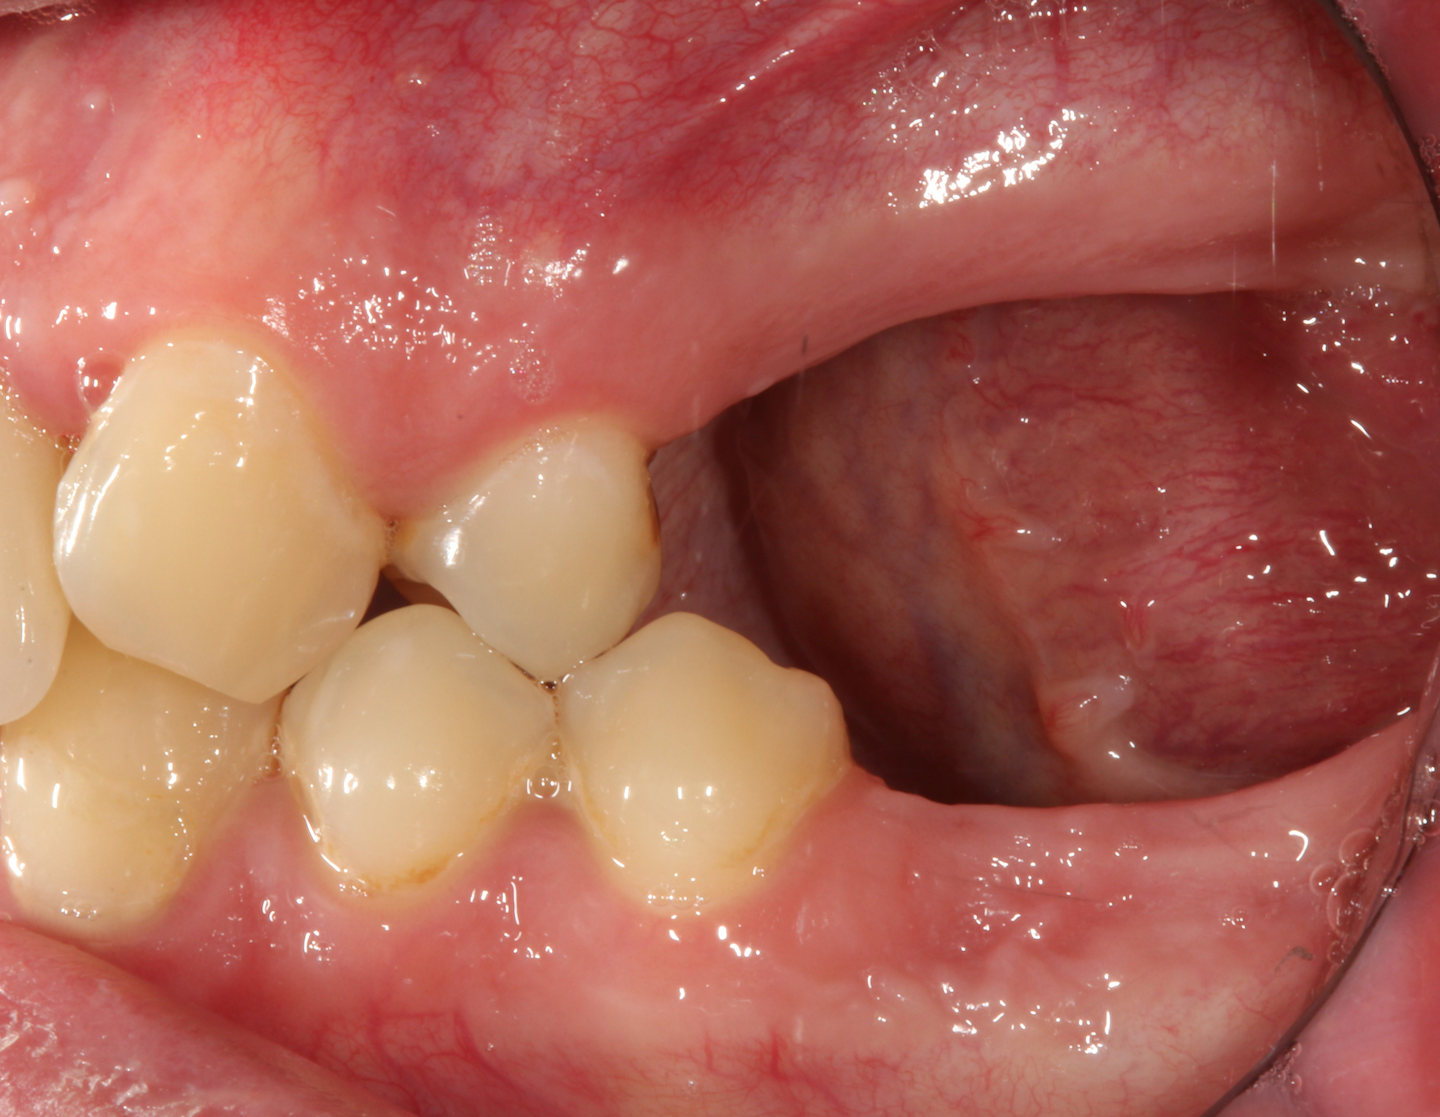

Bone grafting after tooth removal Why, when, and what to use Perio Bone Resorption After Tooth Extraction When, after tooth extraction, this space is occupied by bone or by an implant and. A variable amount of alveolar bone resorption occurs after unassisted socket healing depending on tooth type. Teeth extraction is leaded by alveolar bone resorption which rapidly begins and continues for years. The four stages of healing actually progress at a relatively fast rate in humans. Bone Resorption After Tooth Extraction.